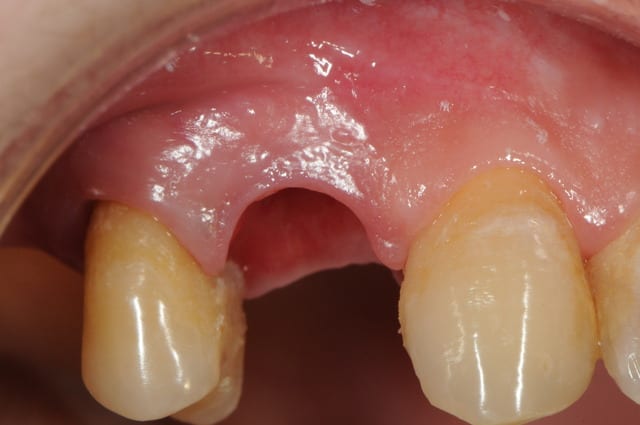

çà manque un peu de cas en ce moment...alors en voilà un ptit au passage...

11 avec résorption interne

EII avec MCI sur du dentium (4.5/14) comblement du gap vestibulaire avec du kasios tcp (très constant dans les résultats...et très économique)

pas de photos de chir par contre...j'ai du les effacer par erreur...grrrr...

la prothèse d'usage a été réalisée par ma petite associée...mais j'étais là pour superviser et faire quelques photos...;-)